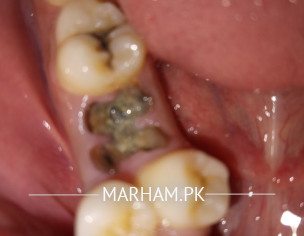

Walikum asalam.. dekhe apki batai history se to mujhe itna clearly samj nahi a raha ke condition kya hai magar ap mujhe apne teeth ki picture send kar lein to main dekh kar apko treatment bata sakta hu. Aur behtar ye hoga ke proper treatment ke leye ap mere clinic visit kar lein to main proper history aur examination kar saku ga

sap ka first molar tooth carious he is liye second molar tooth ko braces ke Sath move kerna Hoga.

I would suggest that you should go for a detailed dental check up. If the tooth, which is extra in your mouth, is in good condition then it can replace the broken down tooth then braces could be a possibility. However, keep this thing in mind that orthodontic treatment is not only for one teeth it affects and corrects your whole dentition.

You need proper checkup and xrays and yes this can be corrected by Braces.